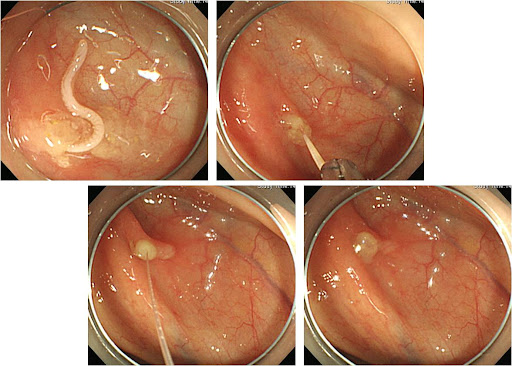

- 내시경 제거: 병원에서 내시경을 통해 위벽이나 장벽에 박힌 고래회충을 제거합니다.